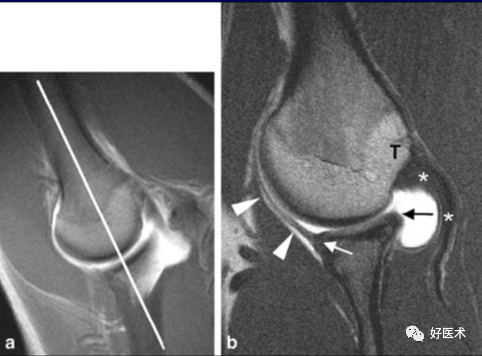

1.Bankart lesion

盂肱下韧带和前盂唇(前下盂唇韧带复合体)从关节盂边缘撕脱,伴肩胛骨骨膜的撕裂。首次损伤后不恰当愈合可导致反复肩关节不稳。

2.Bony Bankart lesion

前下盂唇韧带复合体从关节盂边缘撕脱,伴继发于前关节脱位的肩胛盂骨性骨折。

3.Perthes lesion

Bankart lesion的变异:前下盂唇韧带复合体从关节盂边缘脱离,但骨膜完整且向前内侧剥脱,因此盂唇可在正常解剖位置。